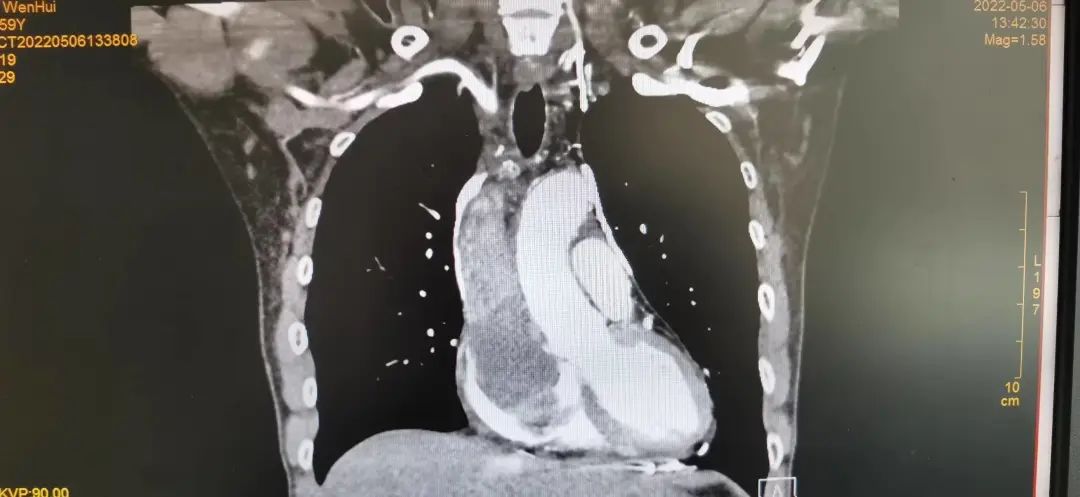

阴影处显示,肿瘤已侵蚀到上腔静脉及心脏

通过穿刺活检,朱伯被确诊为A型胸腺瘤,而且病情复杂,手术难度大、风险高。